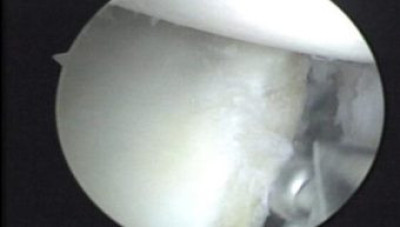

Se ha introducido un pin metálico en la zona de colocación de tornillos, los cuales serán de dos a tres en la zona de 3 a 5 ½ en hombro derecho y de 6 ½ a 9 en el hombro izquierdo según las agujas del relog